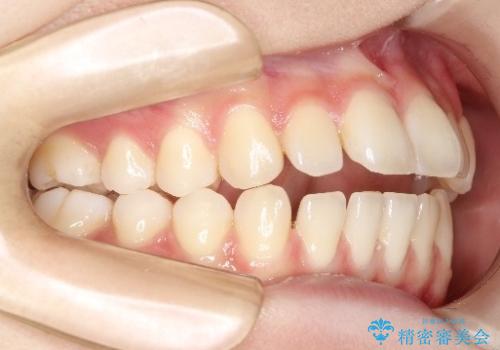

【前歯で噛めません、すきっ歯も気になります】インビザライン治療症例

- 前歯の見た目と噛み合わせの改善を希望され来院された患者様です。

初診時の歯並びの状態としては、上下前歯が噛んでいない開口という状態であり、前歯を中心に上下とも歯の間に隙間がある状態でした。

抜歯は行わずマウスピース治療による主訴の改善を計画しました。

見た目、嚙み合わせ及び、治療期間や施術内容に大変ご満足いただきました。